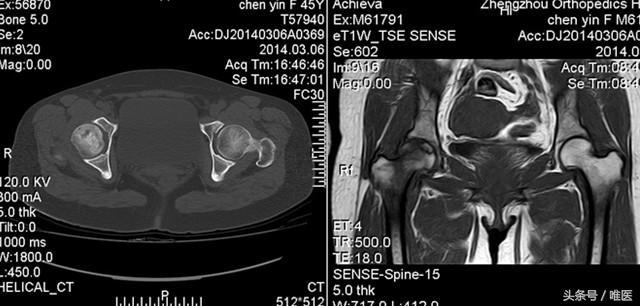

2、影像學檢查:醫生可能會通過X光、MRI等影像學檢查手段來確診股骨頭壞死。